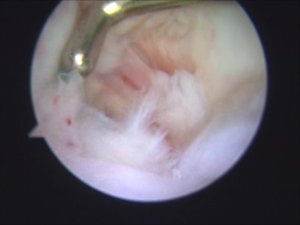

• 膝関節鏡視下手術の併用